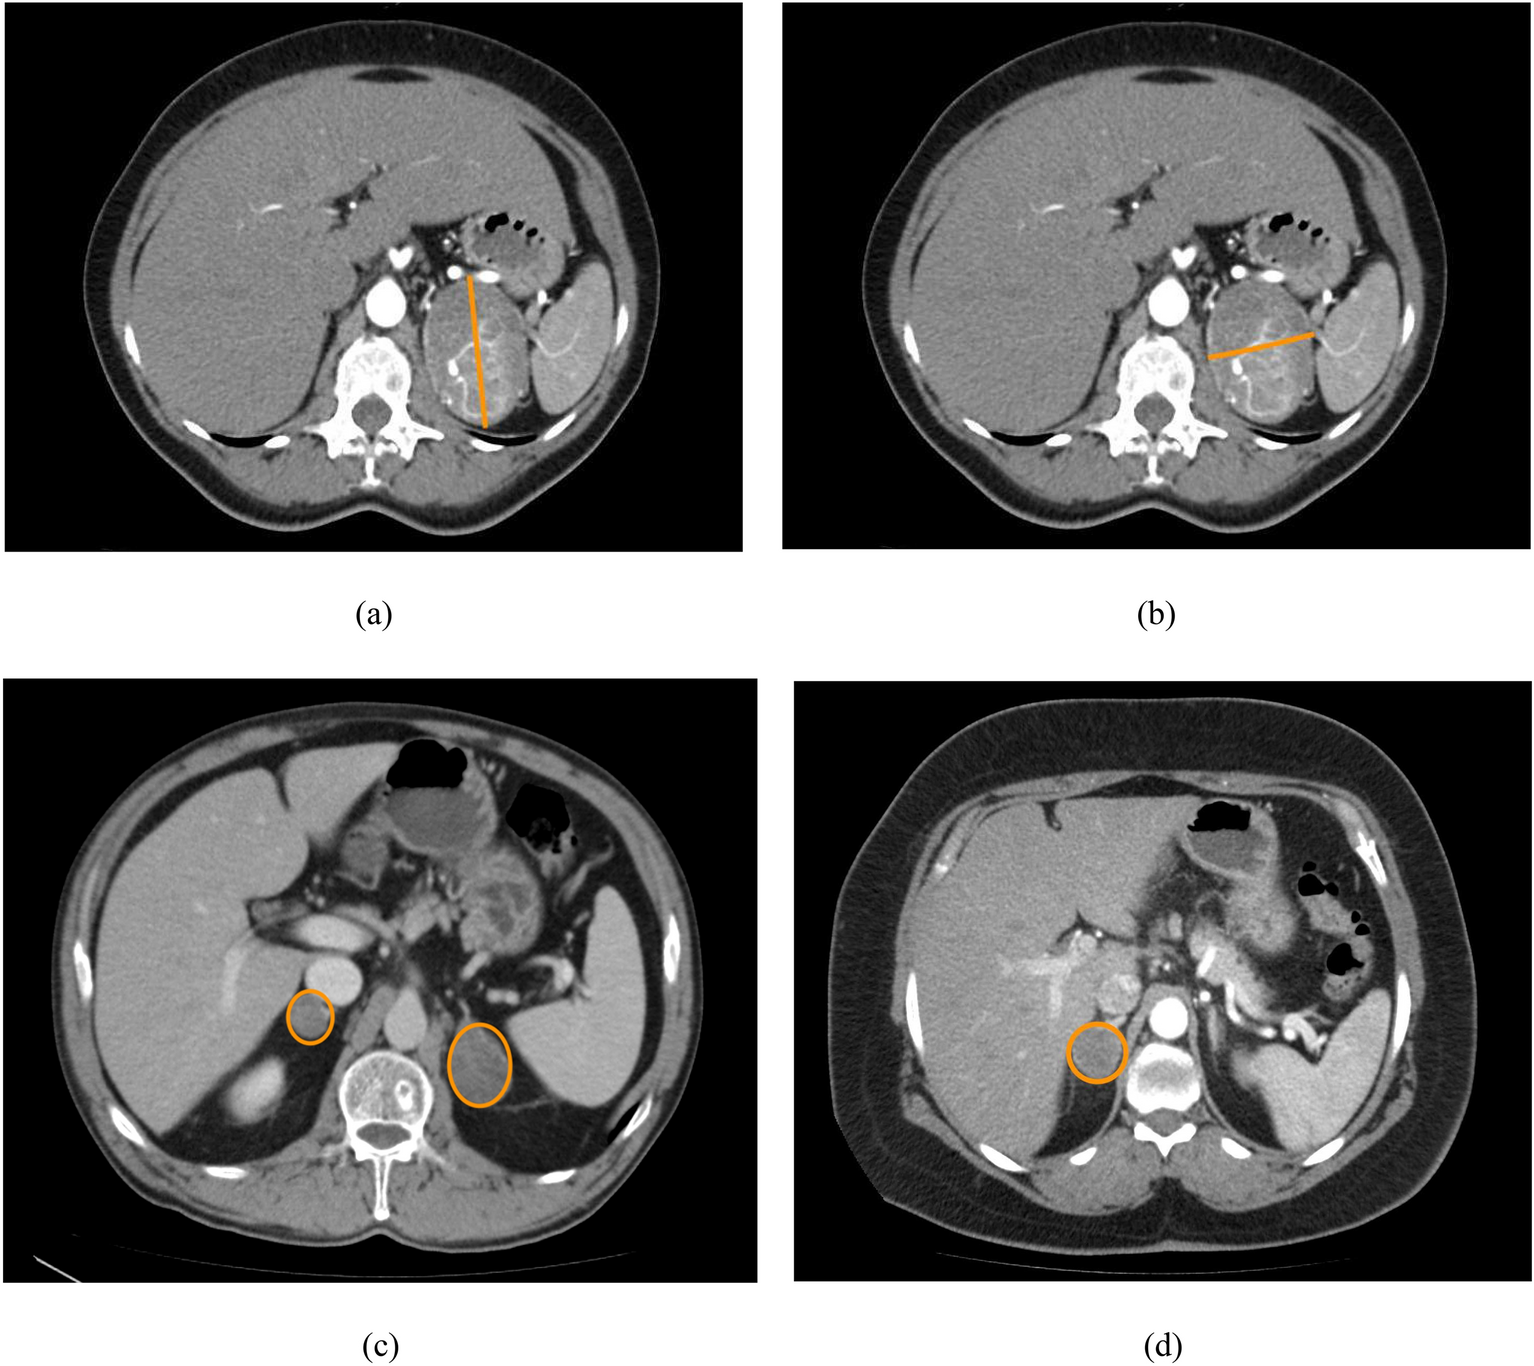

Figure 2

Examples CT image with adrenal tumour showing attributes used in this study: (a) maximal diameter for tumour with homogeneity feature absent and laterization feature present, (b) minimal diameter for tumour with homogeneity feature absent and laterization feature present, (c) tumour with laterization feature absent, (d) tumour with homogeneity feature present.